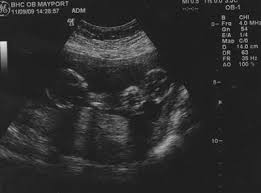

When did you start showing with twins? The average newborn twin weighs 5 1/2 pounds. Lowest prices from hundreds of sites all in one place. Women who are carrying twins or multiples in their wombs tend to have it a tad more difficult than those who are pregnant with a single baby. If your nausea and vomiting is super severe, definitely bring it up to your ob. It might soon be time to shop for a larger, more comfortable bra. As well as the pregnancy symptoms being more severe, they can also occur much earlier on. 3089 grams / 6lbs, 12oz.

3261 grams / 7lbs, 3oz. Nevertheless, make the best of what you can and enjoy the luxury of pregnancy. How did you feel at 13 weeks? As well as the pregnancy symptoms being more severe, they can also occur much earlier on. All your children's organs are developed but are still maturing. Women who are carrying twins or multiples in their wombs tend to have it a tad more difficult than those who are pregnant with a single baby. From week 8 to 12, the last month representing the embryonic stage, your twins are swiftly progressing in their development they will have quadrupled in both length and weight. Estimated fetal weight for twins fetal growth chart fetal weight chart full term for twins twin fetal growth chart twin pregnancy week by week twin pregnancy: 2697 grams / 5lbs, 15oz. What would 13 weeks pregnant feel like? 3089 grams / 6lbs, 12oz. Sep 26, 2018 · the second trimester is officially on once you are 13 weeks pregnant. Twin pregnancy symptoms and conditions.